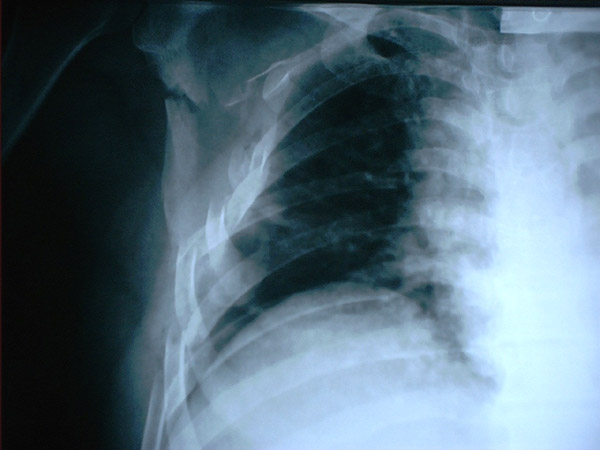

Fractura costal

Fractura costal por caída.

Paquipleuritis. Fractura costal.